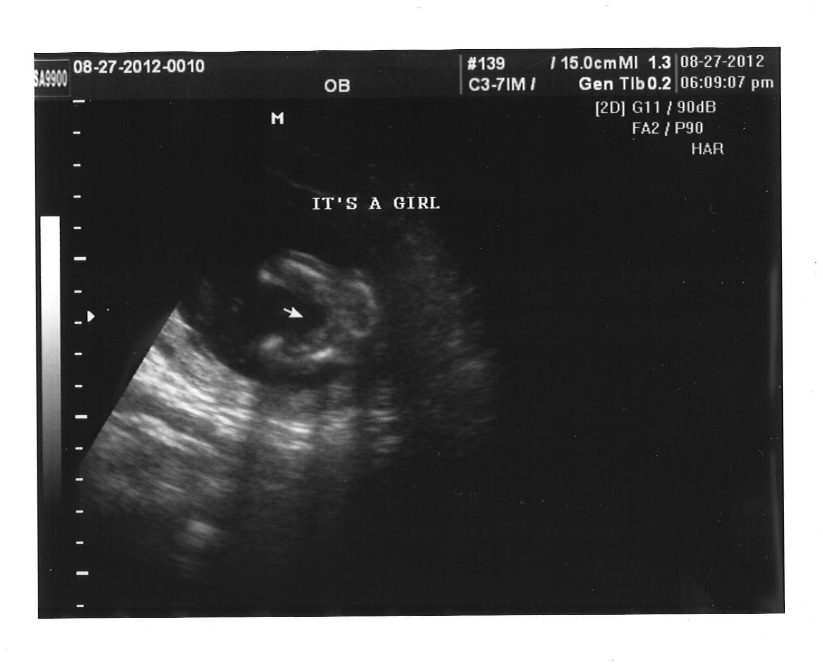

But it's confirmed ladies, IT'S A GIRL!!!!!!! :running:

There were three lines the whole time... nothing between her little legs!